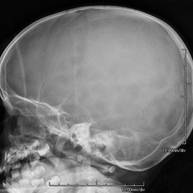

- RX Crani

Tècnica que usa els raigs X a través de la qual s'obtenen imatges del crani per al seu estudi. Indicacions: traumatisme, tancament precoç de sutures cranials. - RX Sins Paranasals